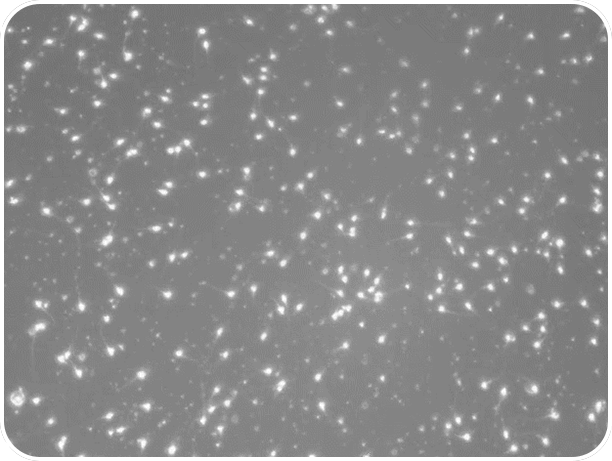

| Spermiogram teszt eredmények | |

| PROfertil® szedés előtt A spermiogram fontos vizsgálati módszer a férfi termékenység felmérésére. Az értékelést a WHO (Egészségügyi Világszervezet) irányelveinek megfelelően végzik. | PROfertil® szedés után A spermiumok koncentrációját, mozgékonyságát, mennyiségét, illetve alakját vizsgálják mikroszkópos eljárással |